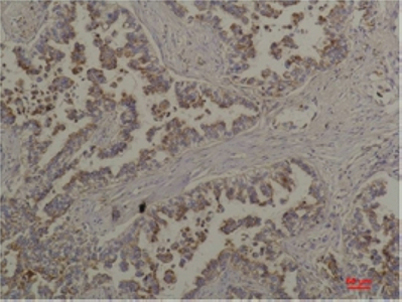

Immunohistochemical analysis of paraffin-embedded Human Lung Carcinoma using Flotillin-2 Rabbit pAb diluted at 1:200

Immunohistochemical analysis of paraffin-embedded Human Lung Carcinoma using Flotillin-2 Rabbit pAb diluted at 1:200